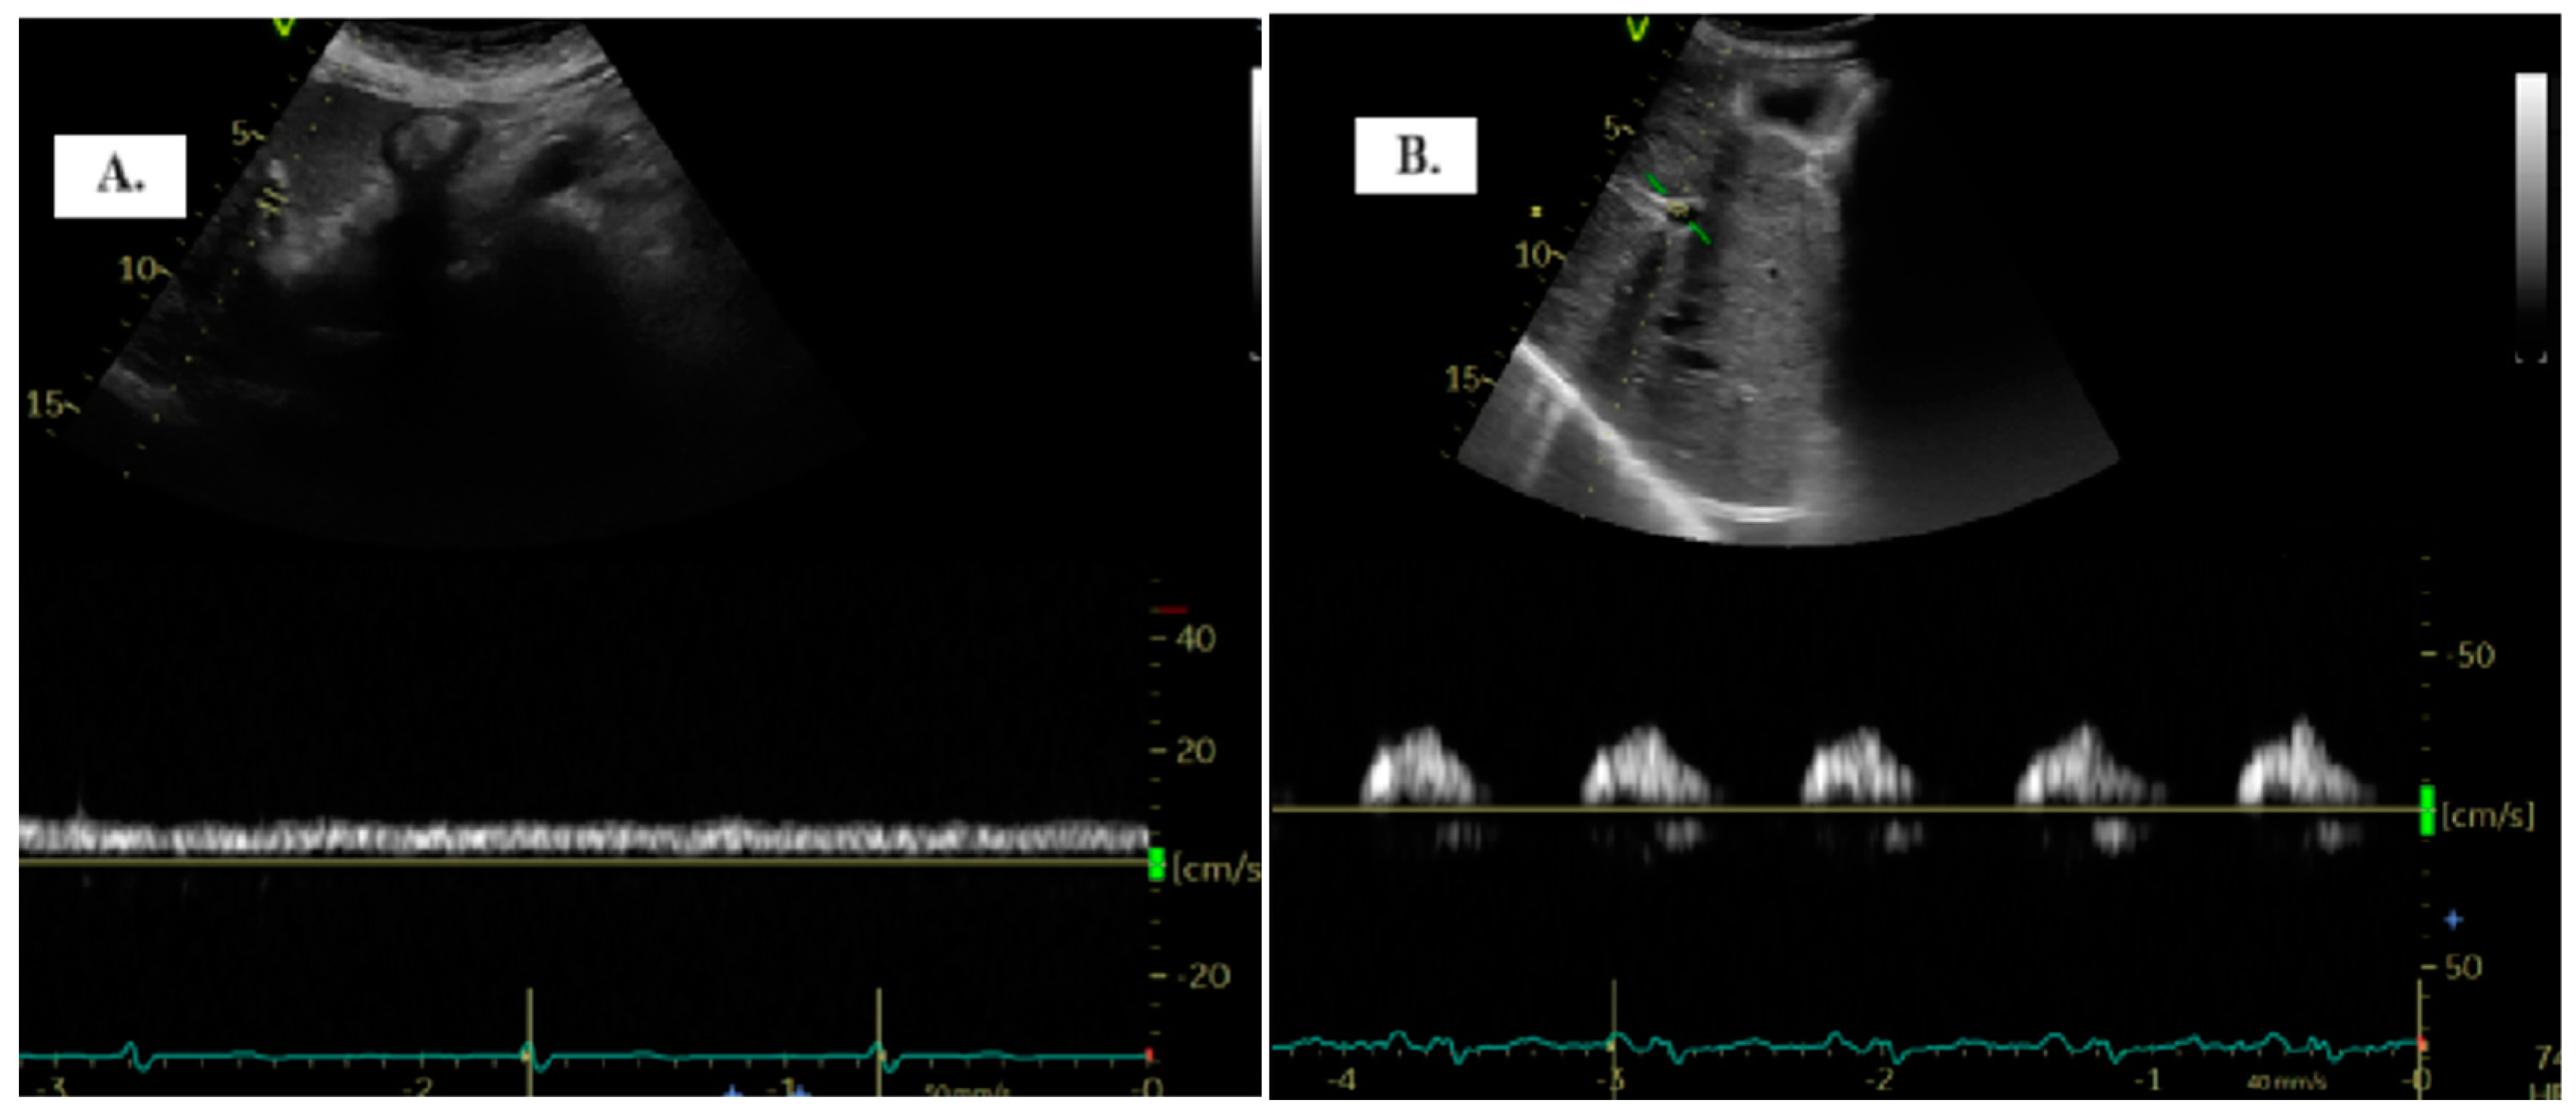

To detect the portal vein (PV), patients were positioned in the dorsal decubitus position in post-expiratory apnea. Either the sub-xiphoid or lateral transhepatic windows can be used for imaging. The PV assessment is conducted using color Doppler and Pulsed-Wave Doppler with a baseline velocity of 20 cm/s, synchronized with the electrocardiogram. Maximum (Vmax) and minimum (Vmin) velocities were measured, and the portal vein pulsatility index (PVPI) was calculated using the formula: maximum velocity − minimum velocity/maximum velocity) × 100 (Figure 1). In some cases, tilting the transducer slightly upward from the mid-axillary transhepatic window helped in visualizing the PV more clearly [9].

Figure 1. The two distinct types of portal vein Doppler patterns: continuous (A) and discontinuous (B).